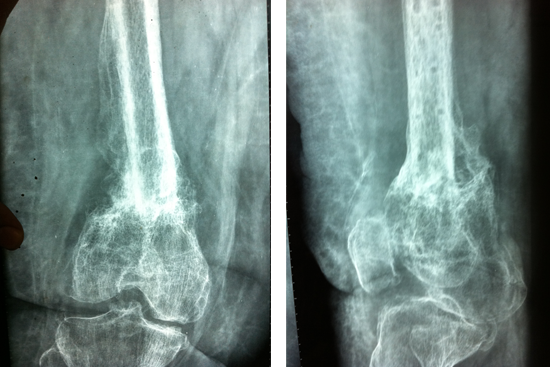

Non Union Femur

Case 1

Case 2 (Rampyari)